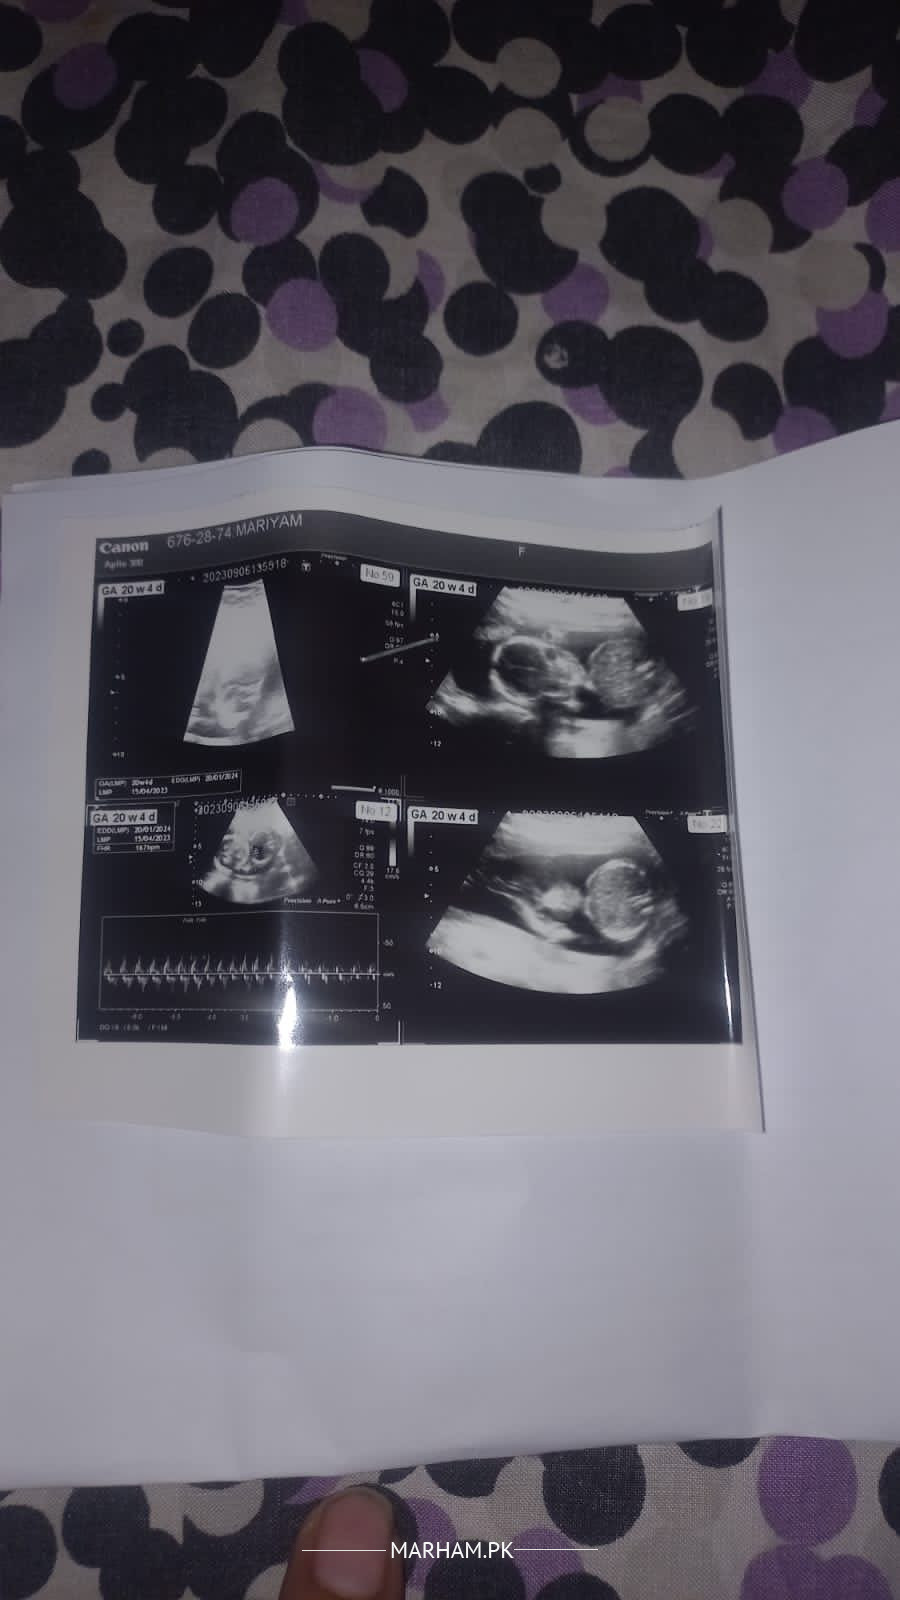

Asalamualikum 20 weeks ki pregnancy hai ye ulrasound kì report hai koi issue tou nahi sb thk hai?

Picture mai report hai ultrasound ki

This is ultrasound report

It is fine

it's ok